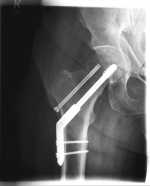

Pertrochanteric fractures, which are not femoral neck fractures close to the hip, are treated with a so-called gamma nail. The rupture here runs through the large and / or small "hillock" (trochanter major and minor) of the thighbone. Here, due to the location of the fracture, the blood supply to the femoral head is NOT compromised. After the operation, an immediate mobilization can take place under pain-adapted full load.

Oberschenkel 5

Picture: In this pertrochanteric femur fracture, a gamma nail was used to stabilize the fracture. The femoral head does not have to be replaced in this case, because the femoral neck is intact and the femoral head is still well supplied with blood.